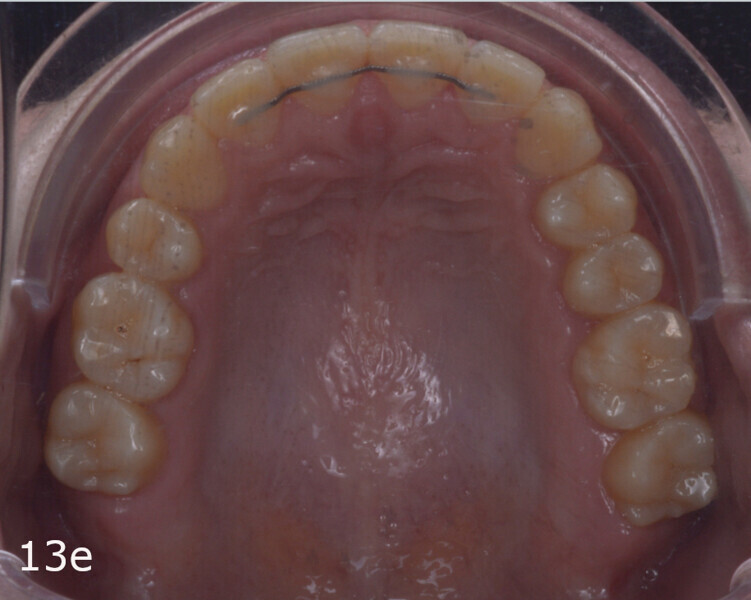

The total treatment time was 15 months. An Angle Class I relationship was established along with adequate anterior and canine guidance, establishing a functional occlusion. This not only ensures optimal masticatory function but also protects the teeth and the temporomandibular joint from excessive force. Maxillary and mandibular fixed retention were installed at the end of the treatment (Figs. 13–19).